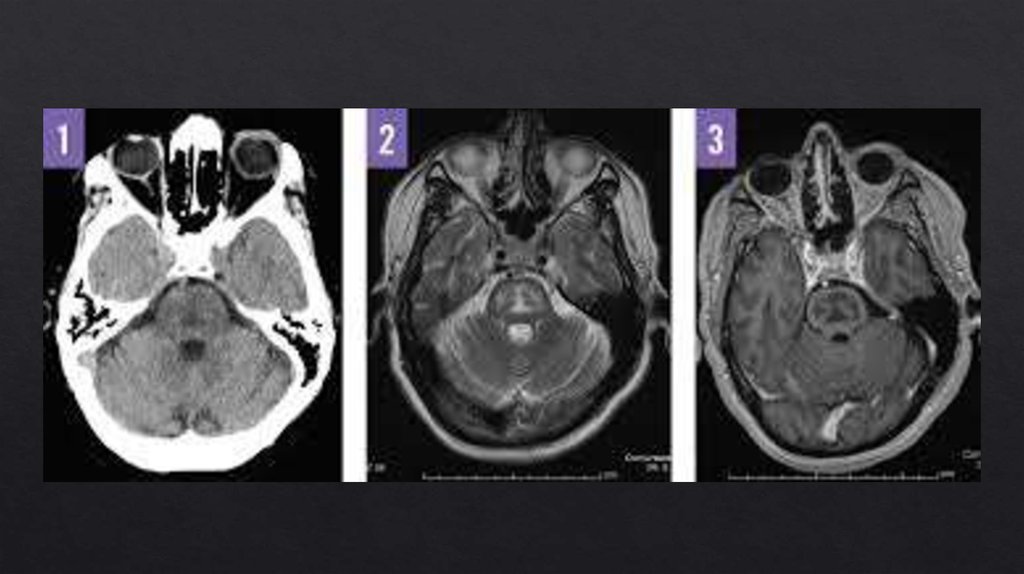

Осмотический демиелинизирующий синдром

23. Осмотический демиелинизирующий синдром